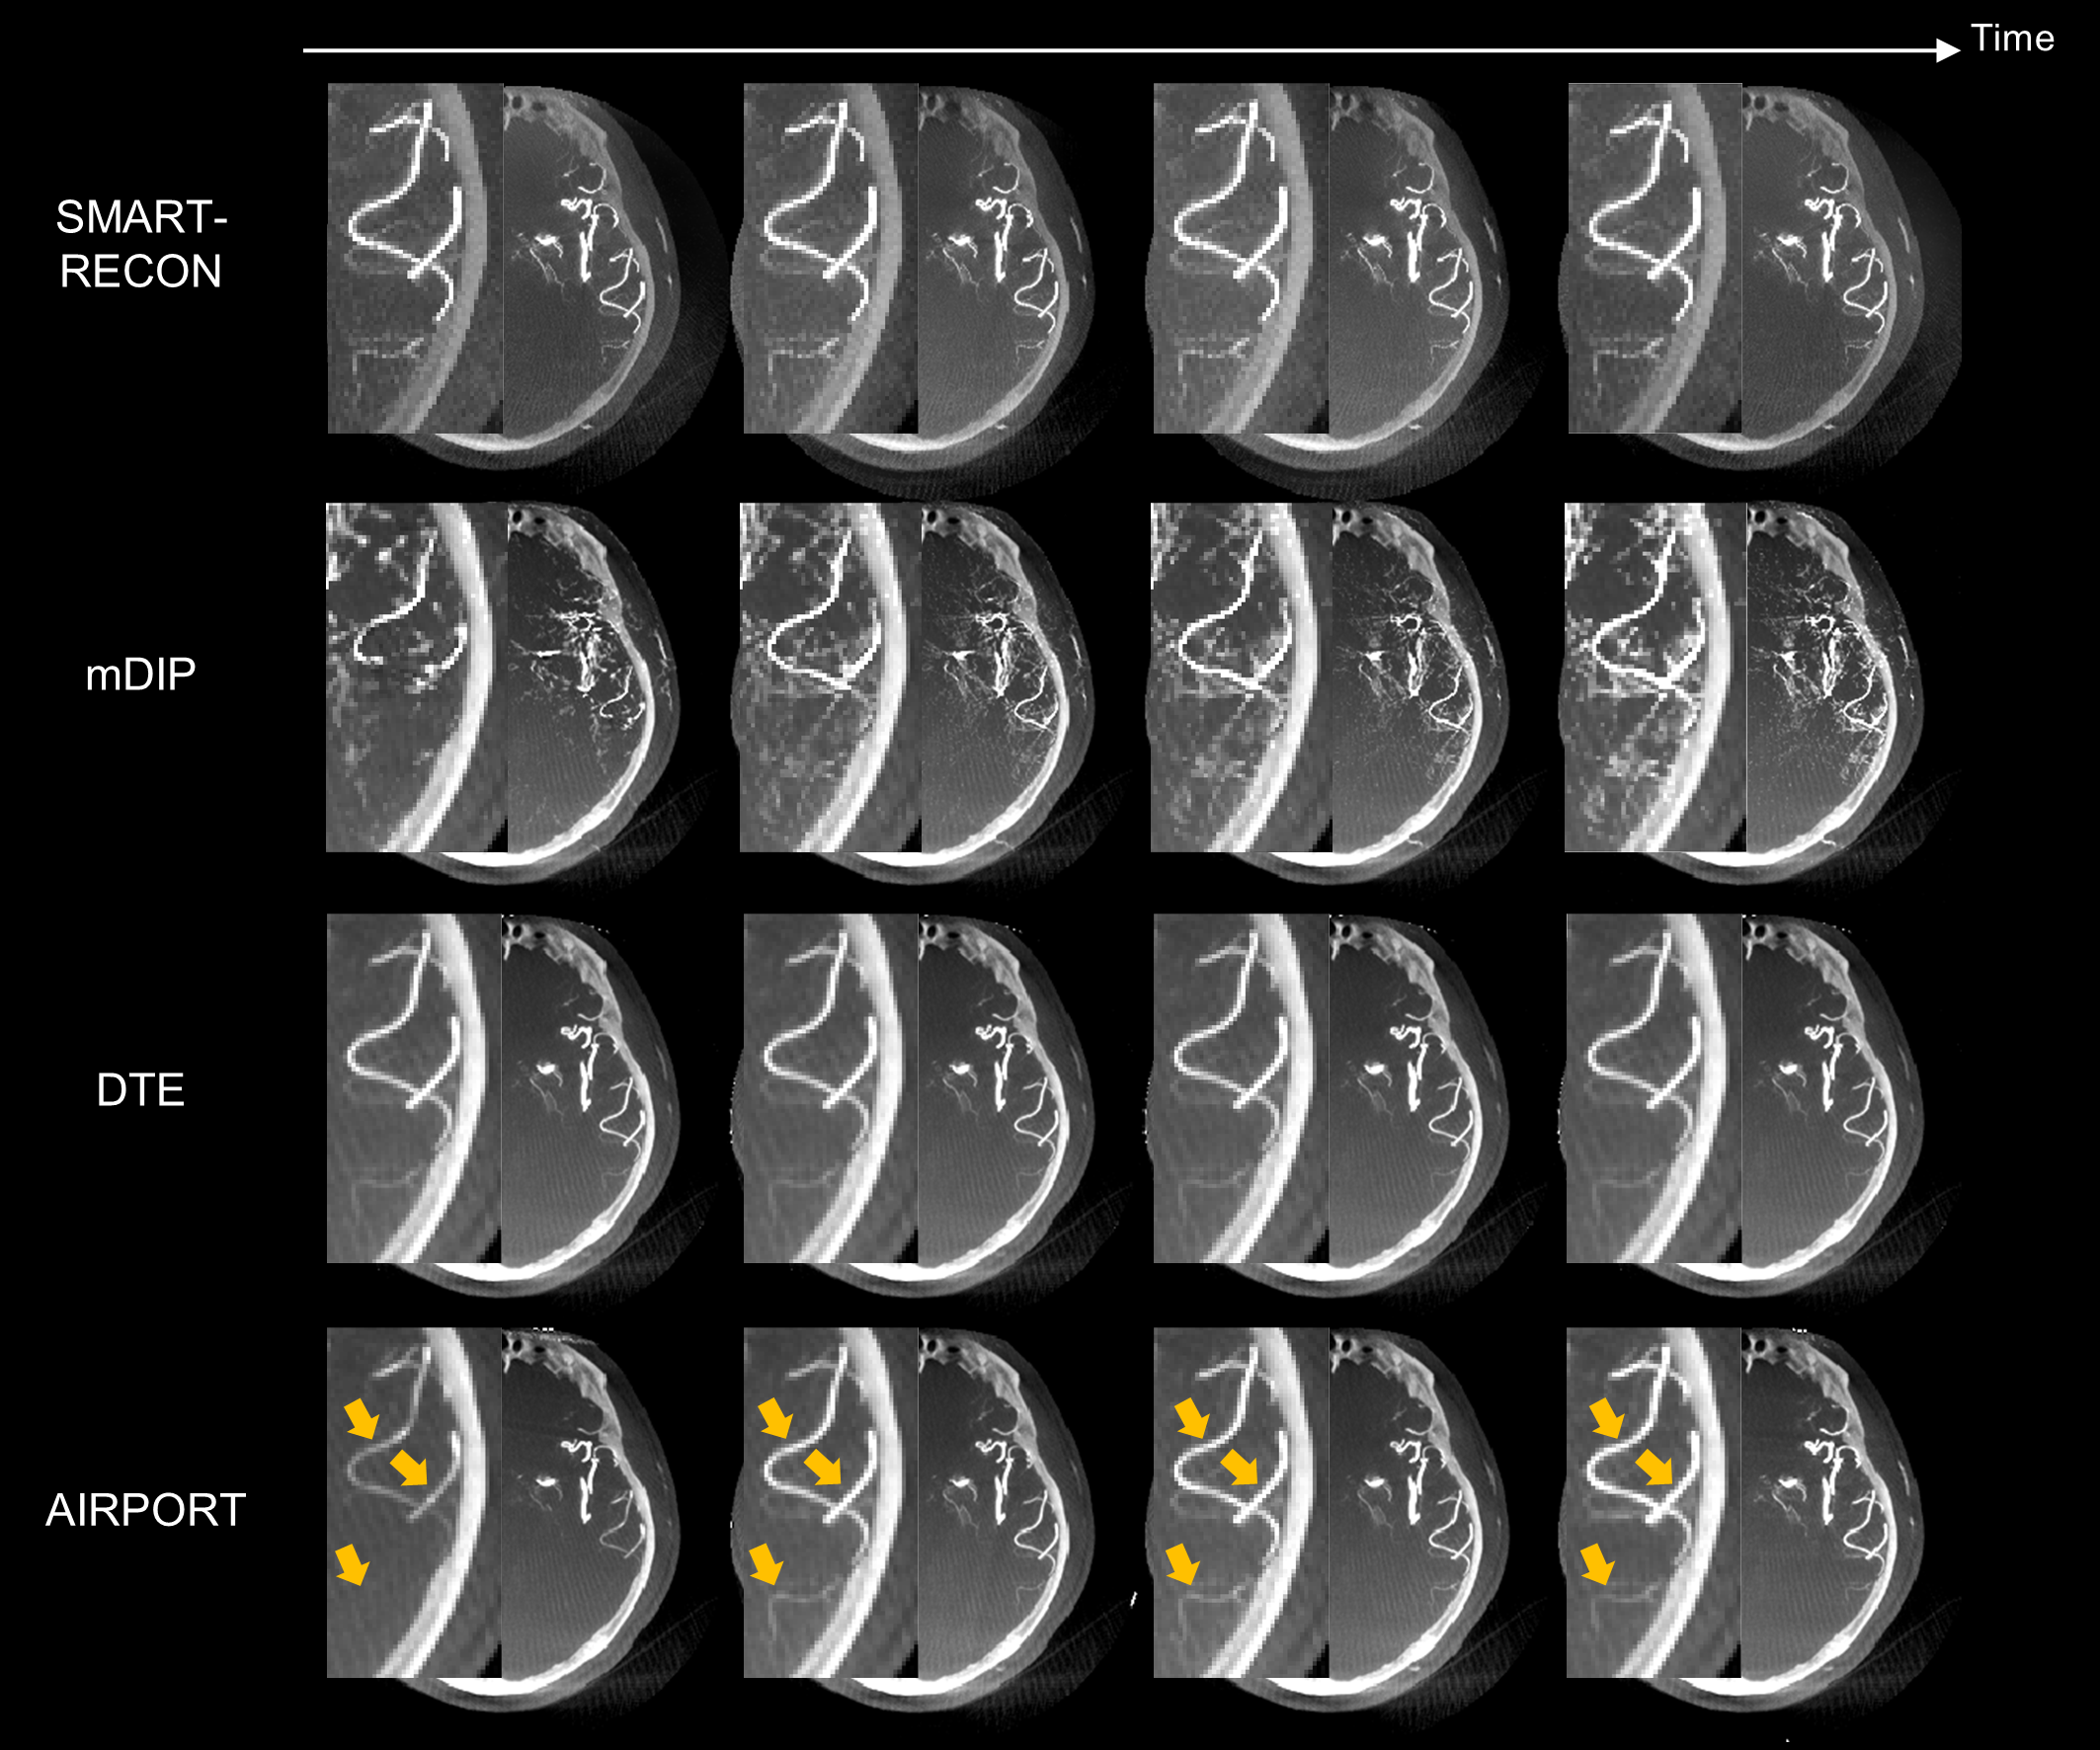

圖3. 人體實(shí)驗(yàn)數(shù)據(jù)結(jié)果。如黃色箭頭所示,提出的AIRPORT方法能夠正確地重建由造影劑注射導(dǎo)致的動(dòng)脈強(qiáng)度值的變化。